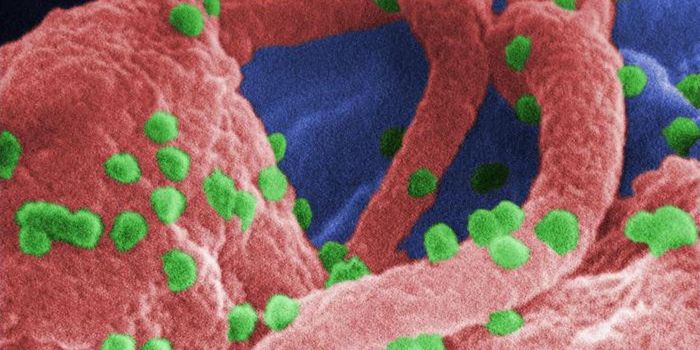

APR 04, 2022Cell & Molecular BiologyAbout 1.5 million new HIV infections are thought to have occurred last year, and while COVID-19 has dominated concerns a ...

FEB 21, 2022Cell & Molecular BiologyTwo people have been cured of HIV, and now, a US woman joins them. In this third case, stem cell transplants were being ...

NOV 30, 2021ImmunologyHIV is a master of disguise. Once the virus enters the body, it has a number of sophisticated mechanisms through which i ...

NOV 22, 2021MicrobiologyThough treatments are available, there is no cure or vaccine from HIV, which impacts about 38 million people worldwide. ...

SEP 06, 2021MicrobiologyHIV vaccines have remained elusive in part because the virus has a powerful ability to mutate, and there are so many str ...

JUN 24, 2021ImmunologyA new study has revealed how stem cells can be used to amplify immune responses to HIV, the virus that causes AIDS. The ...